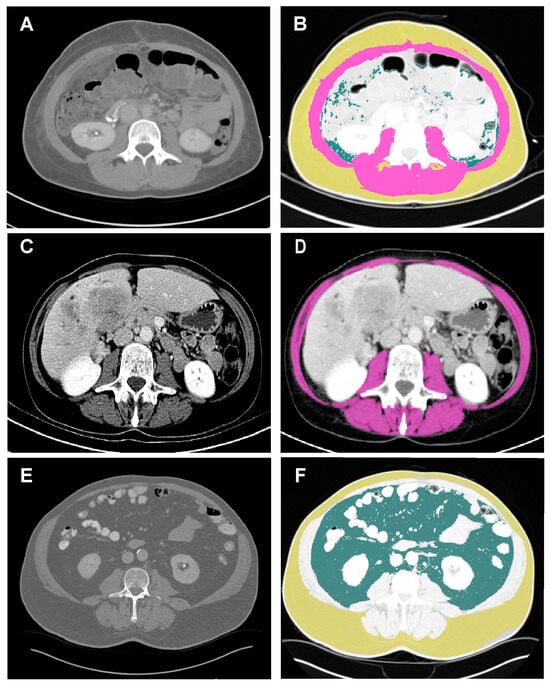

2.2. Body Composition Measurement